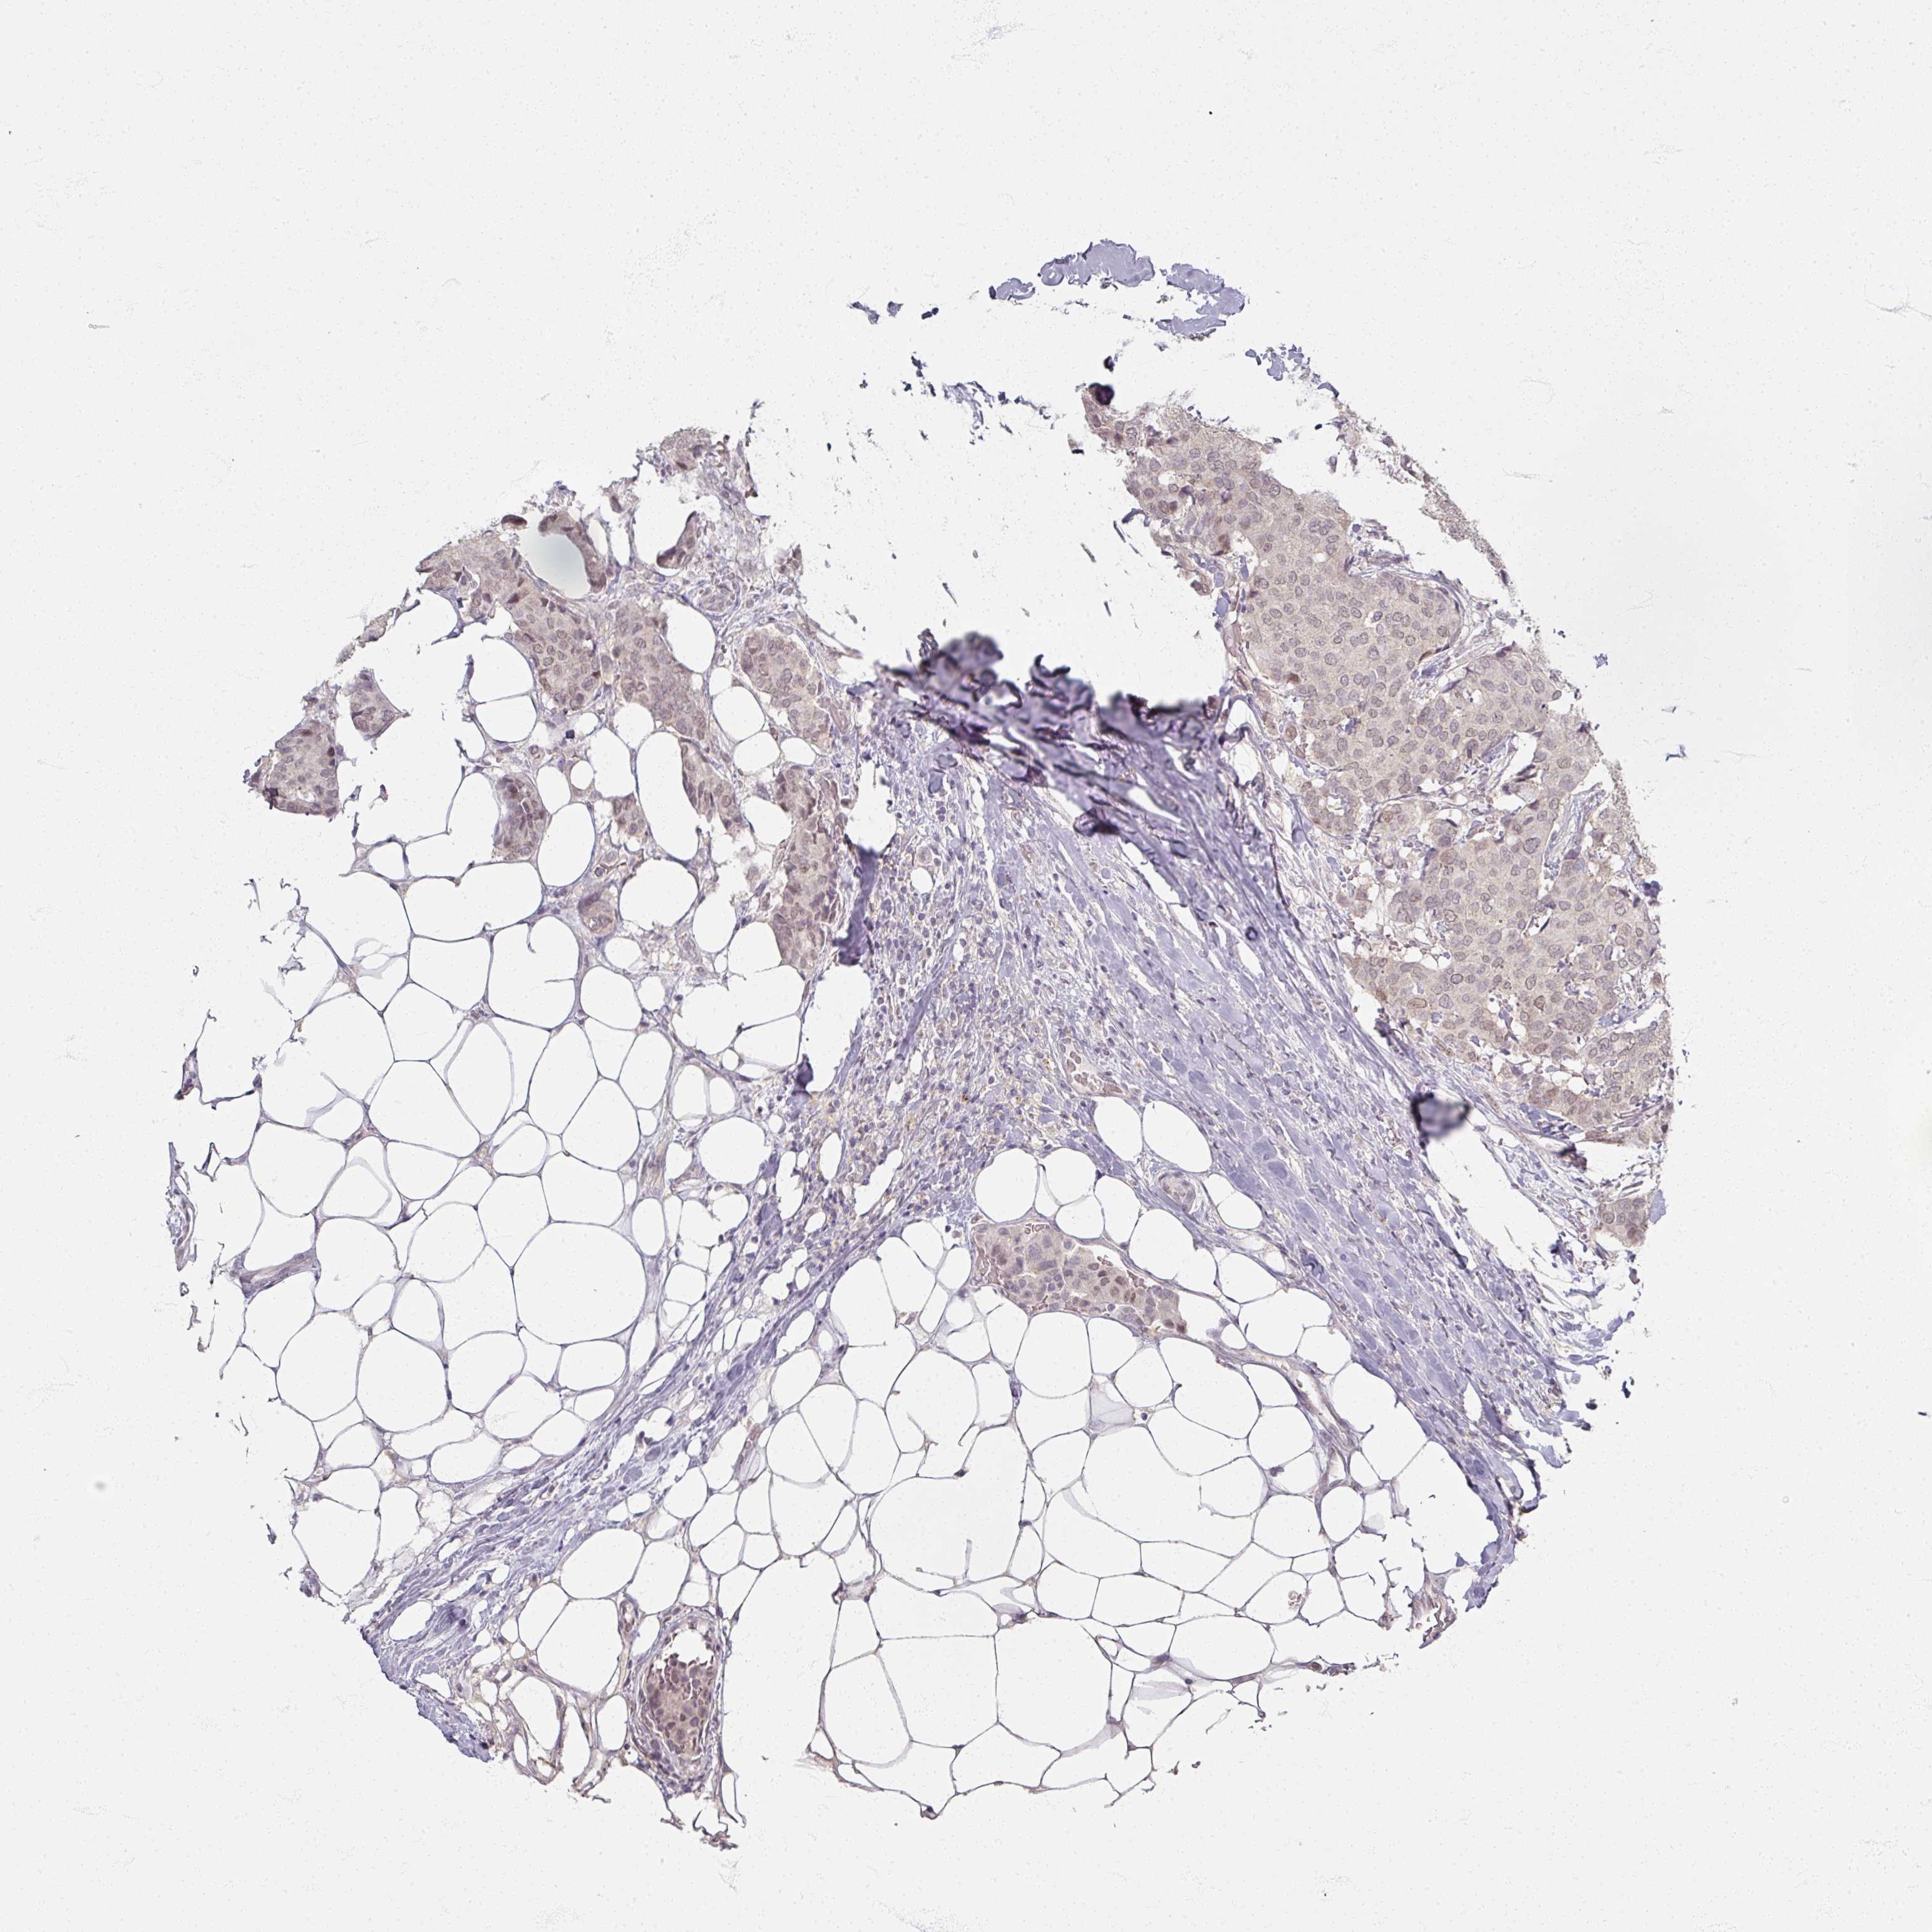

CANCER BREAST CANCER Show tissue menu

BRCA TCGA BRCA VALIDATION PROTEIN EXPRESSION

ANTIBODIES

AND

VALIDATION